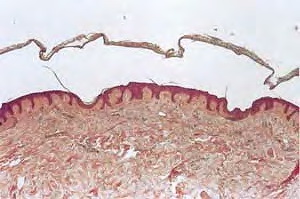

macular-amyloidosis